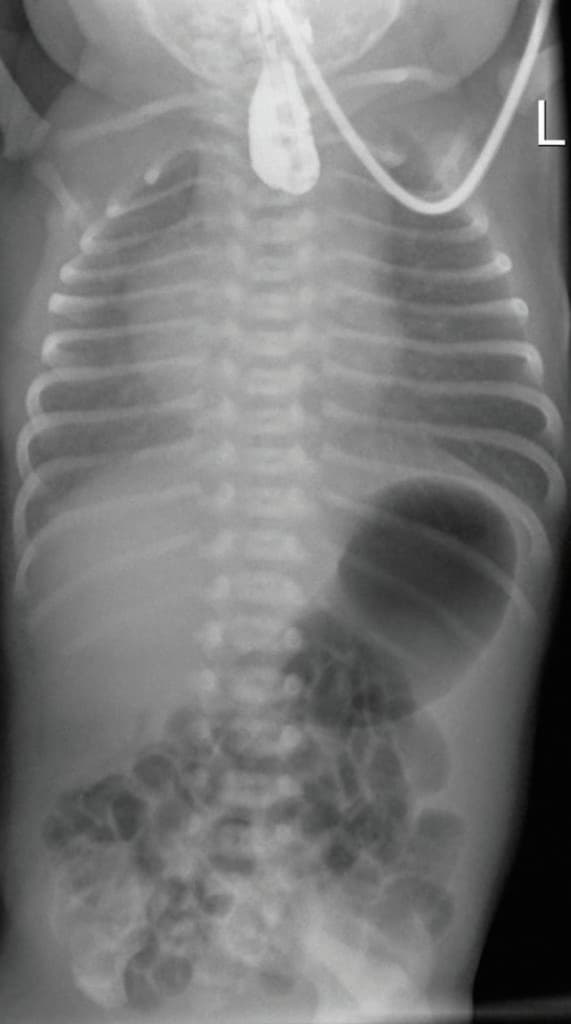

Viel Luft im Magen-Darm-Trakt aufgrund einer Ösophagusatresie.

Angeborene Fehlbildung im Röntgenbild erkennbar

Die Ösophagusatresie ist die häufigste angeborene Anomalie der Speiseröhre. Vermehrtes Speicheln, zyanotische Episoden und Husten weisen darauf hin. Für die Diagnose genügt eine konventionelle Radiologie ohne Kontrastmittel, da sich der Verdacht durch die typische Luftverteilung im Gastrointestinaltrakt sichern lässt (s. Abbildung). Eine Dysphagie bleibt vielfach noch nach einer Operation bestehen, da die Ösophagusmotilitätsstörung anhält und sich an der Anastomose eine Stenose bilden kann.